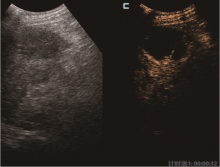

超声造影联合血清CXCL8、CXCR2在原发性肝癌经导管动脉化疗栓塞术后疗效评估中的价值分析

目的 探讨超声造影联合血清CXC趋化因子配体8(CXCL8)、CXC趋化因子受体2(CXCR2)水平检测在原发性肝癌患者经导管动脉化疗栓塞术(TACE)治疗后疗效评估中的应用价值。方法 选取2019年6月至2022年1月湖北省黄冈市中心医院诊治的80例原发性肝癌患者为研究对象,TACE治疗2个月后评估治疗疗效,根据病理诊断结果分为完全灭活组(n=30)和病灶残留组(n=50)。采用酶联免疫吸附双抗体夹心法检测患者血清CXCL8、CXCR2水平,并对患者进行超声造影检查;采用受试者工作特征(ROC)曲线分析血清CXCL8、CXCR2评估原发性肝癌患者TACE治疗后疗效的价值;超声造影及超声造影联合血清CXCL8、CXCR2评估原发性肝癌患者TACE治疗后疗效与病理诊断结果的一致性采用Kappa检验。结果 与完全灭活组比较,病灶残留组血清CXCL8[(7.12±1.68)ng/ml vs. (5.07±1.25)ng/ml]、CXCR2[(3.62±0.79)ng/ml vs. (2.43±0.67)ng/ml]水平均较高(t=5.79,P<0.001;t=6.89,P<0.001)。CXCL8、CXCR2评估原发性肝癌患者TACE治疗后疗效的曲线下面积分别为0.827、0.801,特异性分别为73.3%、76.7%,敏感性分别为70.0%、72.0%。超声造影评估原发性肝癌患者TACE治疗后疗效与病理诊断结果一致性为中度,Kappa值为0.49(P<0.001)。超声造影联合血清CXCL8、CXCR2评估原发性肝癌患者TACE治疗后疗效与病理诊断结果一致性为较高,Kappa值为0.62(P<0.001)。超声造影联合血清CXCL8、CXCR2评估原发性肝癌患者TACE治疗后疗效的敏感性为90.0%,高于超声造影(72.0%,χ2=5.26,P=0.022)、CXCL8(70.0%,χ2=6.25,P=0.012)和CXCR2(72.0%,χ2=5.26,P=0.022)单独评估。结论 超声造影可一定程度检出原发性肝癌患者TACE治疗后的病灶残留,且其联合血清CXCL8、CXCR2可有效提高原发性肝癌患者TACE治疗后疗效的评估效能。

Objective To investigate the application value of contrast-enhanced ultrasound combined with serum CXC chemokine ligand 8 (CXCL8) and CXC chemokine receptor 2 (CXCR2) levels detection in the efficacy evaluation of patients with primary liver cancer after transcatheter arterial chemoembolization (TACE). Methods A total of 80 patients with primary liver cancer who were diagnosed and treated in Huanggang Central Hospital of Hubei Province from June 2019 to January 2022 were selected as the research objects. The therapeutic efficacy was evaluated 2 months after TACE treatment. According to the pathological diagnosis, the patients were divided into complete inactivation group (n=30) and residual lesion group (n=50). The levels of serum CXCL8 and CXCR2 were measured by enzyme linked immunosorbent assay (ELISA) double antibody sandwich method, and contrast-enhanced ultrasonography was performed on the patients. Receiver operating characteristic (ROC) curve was applied to analyze the value of serum CXCL8 and CXCR2 in evaluating the efficacy of TACE in patients with primary liver cancer. Kappa test was applied to test the consistency of contrast-enhanced ultrasound and contrast-enhanced ultrasound combined with serum CXCL8 and CXCR2 in evaluating the efficacy of TACE in patients with primary liver cancer and the results of pathological diagnosis. Results Compared with the complete inactivation group, the levels of serum CXCL8 [(7.12±1.68) ng/ml vs. (5.07±1.25) ng/ml] and CXCR2 [(3.62±0.79) ng/ml vs. (2.43±0.67) ng/ml] in the residual lesion group were obviously higher (t=5.79, P<0.001; t=6.89, P<0.001). The areas under the curve of CXCL8 and CXCR2 in evaluating the efficacy of TACE in patients with primary liver cancer were 0.827 and 0.801 respectively, the specificities were 73.3% and 76.7%, and the sensitivities were 70.0% and 72.0% respectively. The concordance between contrast-enhanced ultrasound and pathological diagnosis was moderate, and the Kappa value was 0.49 (P<0.001). The concordance between contrast-enhanced ultrasound combined with serum CXCL8 and CXCR2 and pathological diagnosis was high, and the Kappa value was 0.62 (P<0.001). The sensitivity of contrast-enhanced ultrasound combined with serum CXCL8 and CXCR2 in evaluating the efficacy of TACE in patients with primary liver cancer was 90.0%, which was higher than the sensitivity of contrast-enhanced ultrasound (72.0%, χ2=5.26, P=0.022), CXCL8 (70.0%, χ2=6.25, P=0.012) and CXCR2 (72.0%, χ2=5.26, P=0.022). Conclusion Contrast-enhanced ultrasound can detect residual lesions after TACE in patients with primary liver cancer to a certain extent, and its combination with serum CXCL8 and CXCR2 can effectively improve the evaluation efficiency of the efficacy of TACE treatment in patients with primary liver cancer.